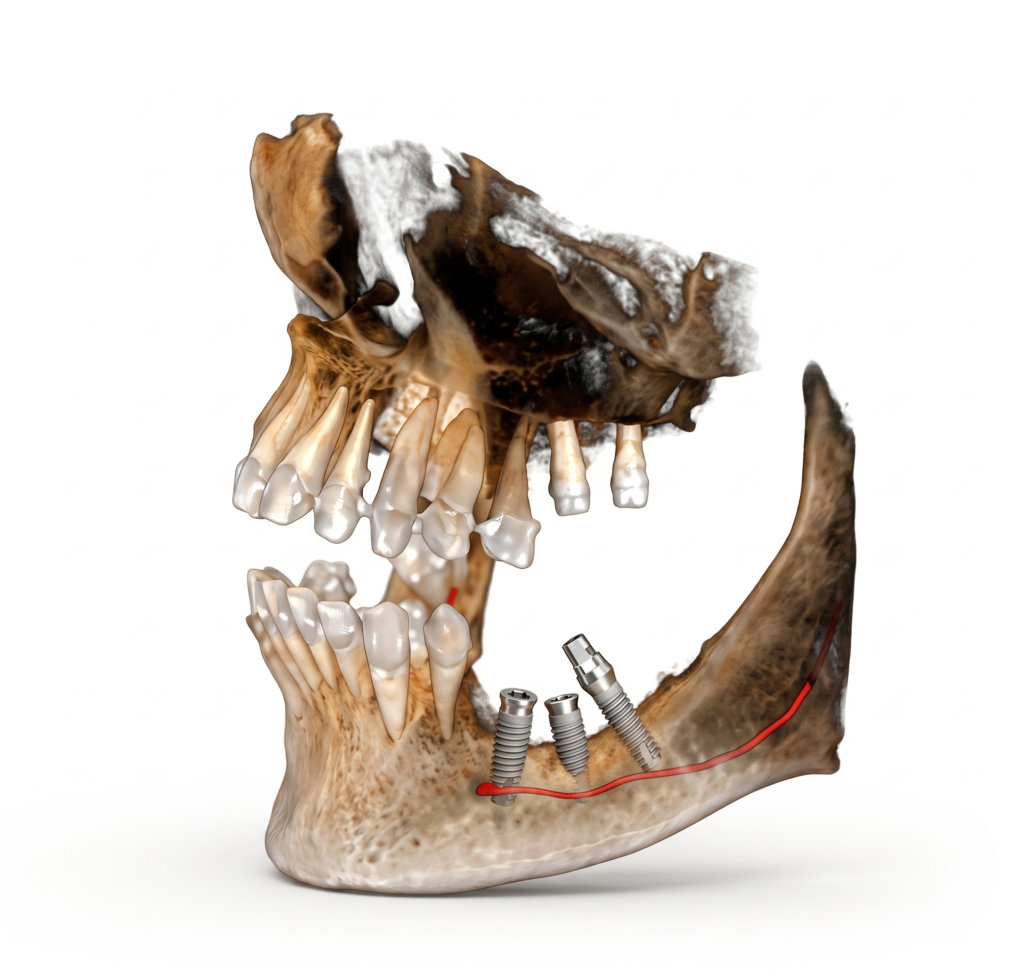

He is certified in Cone Beam Computed Tomography (CBCT) and has extensive experience in advanced radiological diagnosis. Dr. Singh is associated with several reputed centers across India as a consultant radiologist for CBCT reporting. His expertise includes implant planning, impacted teeth localization, oral and maxillofacial pathology interpretation, TMJ assessment, maxillary sinus evaluation, and airway analysis.

Single tooth CBCT 1000/-

Single tooth (If impacted or partially impacted) 1500/-

Quadrant CBCT 1500/-